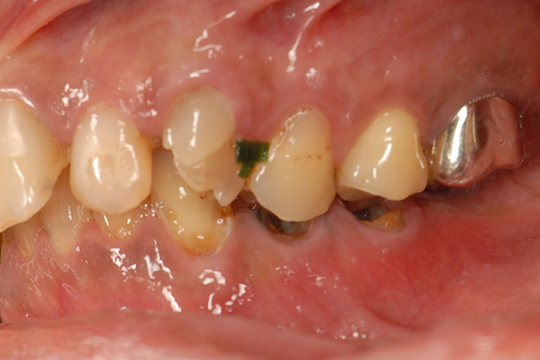

お口の中を5種類のアングルからカメラで撮影します。目視では確認できないところも確認することができます。また、お口の中を患者様ご自身で確認していただくこともできます。